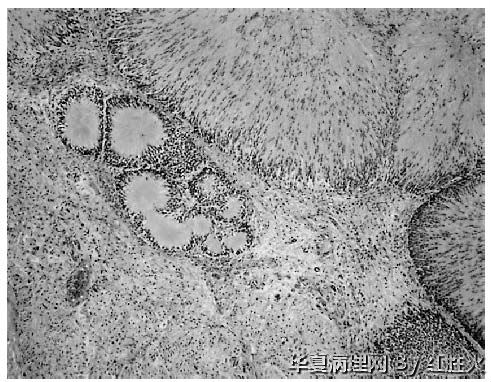

经典型神经鞘瘤容易诊断,而多种特殊亚型(包括陈旧性或退变性神经鞘瘤;细胞性神经鞘瘤;丛状神经鞘瘤;上皮样神经鞘瘤;色素性神经鞘瘤;胃肠道型神经鞘瘤;腺样神经鞘瘤和假腺样神经鞘瘤;微囊状/网状型神经鞘瘤和神经母细胞瘤样神经鞘瘤等)少见或罕见,形态特殊,可造成诊断困难或未被认识,原野所提供的病例恰好可引起我们对此类肿瘤的重视,对开拓思路大有益处。文献报道的神经母细胞瘤样神经鞘瘤图像如下,供参考

本例具有部分经典神经鞘瘤的形态特点,如有细胞密集区和疏松黏液样区、血管壁透明变性;又有其特殊形态,既可见菊形团样结构。因而争论的焦点在于是上皮样神经鞘瘤不是神经母细胞瘤样神经鞘瘤,这两种神经鞘瘤的亚型分别于1998和1994年见于文献报道,本例虽有菊形团样结构,但菊形团较小不够突出,另外其瘤细胞胞质较为丰富呈上皮样(神经纤维瘤样神经鞘瘤的瘤细胞缺少胞质),HE形态诊断上皮样神经鞘瘤更为客观,加做Ⅳ型胶原如能显示瘤细胞周围的基底膜样物质,则可进一步证实。